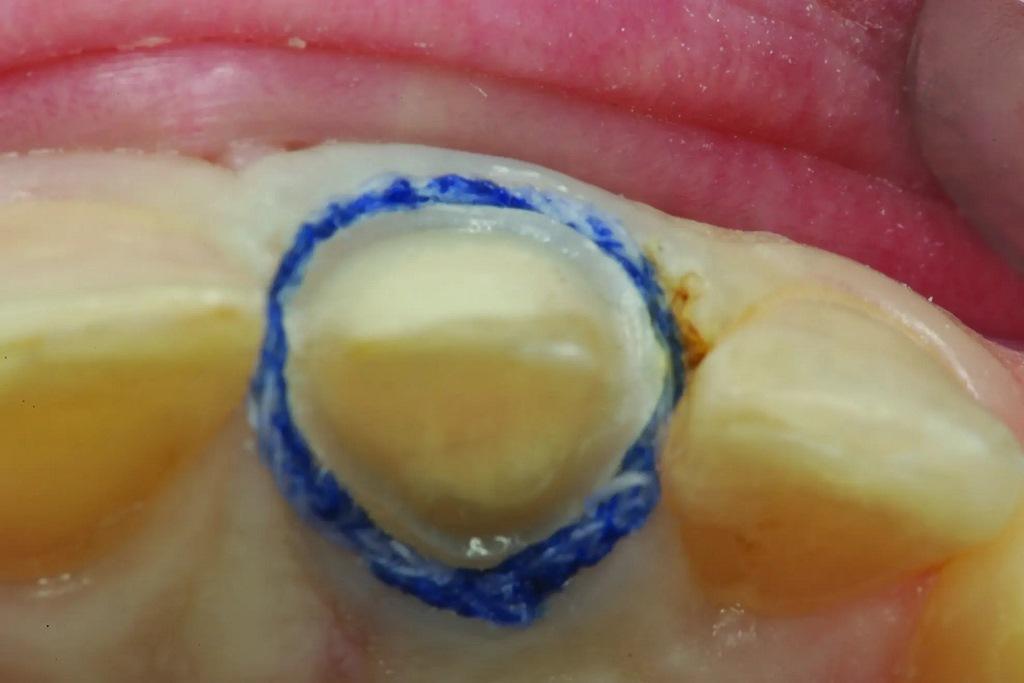

В данном случае, после установки ретракционной нити 1, в лицевой области препарирования образовался избыток ткани, который, возможно, препятствовал прохождению поддесневого оттискного материала. Сверхимпульсный диодный лазер (Gemini, Ultradent Products) использовался для тщательного удаления излишков ткани, прилегающей к нити, без повреждения нити (фото 12-13). Ретракционная нить была полностью видимой перед удалением, что обеспечивало беспрепятственный доступ легкого оттискного материала в отведенную область.

Фото 12: С помощью сверхимпульсного диодного лазера удаляют излишки ткани, надрезая верхнюю нить.